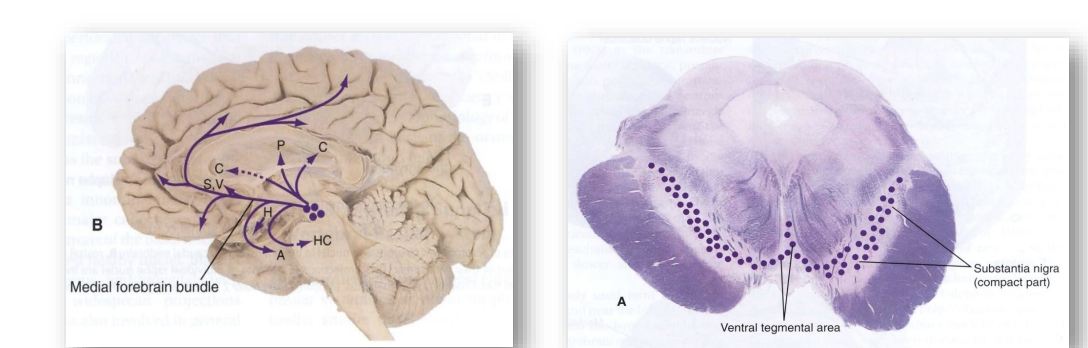

• Dopamine neurons in the substantia nigra and the ventral tegmental area project (from the substantia nigra) to the striatum and (from the VTA) to the nucleus accumbens and prefrontal cortex.

• dopamine neurons are clustered in the brainstem

• substantia nigra projects (lateral in brainstem) to putamen and caudate nucleus (parts of BG involved in movement). Neurons that degenerate in Parkinsons. Called the Nigrostriatal pathway.

• Ventral tegmental area (medially located) projects to nucleus accumbens which is involved in behaviors associated with rewards. Anything that causes a positive effect caused release of dopamine in the nucleus accumbens nigrastriatal neurons project up to the frontal lobe (more involved in cognition and regulating behaviour).